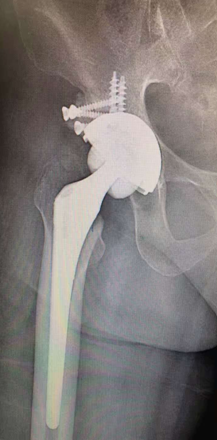

我科为国家中医药管理局“十二五”重点专科建设单位。拥有进口关节镜全套设备、髋膝肩肘人工关节置换全套体系、TDP治疗仪、电脑中频透热治疗仪、多功能微波治疗仪、中药煎药机、下肢功能锻炼机等诊疗设备。根据国内外关节外科发展方向,充分应用中医药发展优势,创立中西医结合特色。近年来已开展了髋、膝、肘、肩等关节人工置换术1000余例,每年各种关节置换100多例,各种关节镜微创手术、运动损伤致各种肌腱、韧带损伤修补重建手术200余例及各种关节骨折内固定手术近400余例,数量和质量居市内各大医院前列。本科室主持两项自治区科研课题两项,市科研6项,在国家杂志发表论文60余篇,研究了跌打散、郁金散、跌打郁金膏、驳骨膏、跌打追风酒、损伤外洗合剂等二十余种纯中药制剂,为满足患者术后快速康复需要,进一步开发了中药止痛贴、消肿贴、痛风贴等外用制剂,广泛运用临床。

①四肢骨关节疾患的人工关节置换及翻修治疗;

擅长中西医结合治疗骨科各种疑难疾病:骨质疏松、慢性腰腿痛、运动损伤、各种关节疾病、复杂关节内骨折、运动损伤、儿童骨骼发育异常等疾病。专长:髋、膝、肩等关节置换、翻修术,复杂关节骨折固定术、前后交叉韧带、半月板损伤、肩关节、踝关节等韧带重建微创手术。

擅长各种髋、膝、肘、肩等人工关节置换术,各种复杂人工关节翻修术,各种脊柱疾病内固定手术,各种先天性关节畸形矫形术,复杂骨折内固定手术,骨关节疾病,运动创伤的关节镜诊断治疗技术。

硕士研究生,先后毕业于上海中医药大学、广西中医药大学,师从广西名中医靳嘉昌教授、国务院特殊津贴专家查振刚教授。曾于暨南大学附属第一医院、日本熊本机能病院进修学习。中国中医促进医学会骨坏死专业委员会委员、广西中医药学会中医骨伤科专业委员会委员、广西中医药学会运动医学分会委员、桂林医学会骨科分会委员。擅长运用中西医对四肢、关节及脊柱疾病的诊断和治疗,对各种骨折切开复位内固定术、髋膝关节置换、关节镜微创手术、骨折脱位手法整复有一定的研究。

擅长于髋、膝关节微创置换、脊柱、四肢关节、四肢骨折等疾病的中西医结合诊治;对微创单髁置换、膝关节置换、微创DAA手术,髋膝翻修手术、颈、胸、腰等脊柱内固定手术、关节镜下膝、踝、肩、腕等关节微创手术及ERAS快速康复及中医在骨关节疾病、脊柱相关疾病等有丰富的手术及诊治经验,且在小针刀等中医特色疗法有独到的经验。